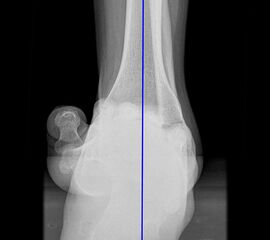

Saltzman Rückfußachsaufnahme (Hindfoot alignment view)

Rückfuß-Alignement-Aufnahmen sind eine wichtige Ergänzung zur Diagnostik von Kalkaneusfehlstellungen (Varus und Valgus), sowie bei der Planung von Rückfußkorrekturen 14.

Indikation:

• Beurteilung der Rückfußachse.

Positionierung:

• Der Patient steht auf einem Podest, beide Beine sind gleichmäßig belastet.

• Die Fußachse ist entlang des Zentralstrahls ausgerichtet.

• Die Röntgenröhre befindet sich dorsal des Beines.

• Röntgenkassette 20° gekippt zur Vertikalen, im 90°-Winkel zum Zentralstrahl.

• Der Zentralstrahl ist von dorsal auf das obere Sprunggelenk fokussiert.

Kennzeichen des Röntgenbildes:

• Markieren der Tibiaachse mit Verlängerung nach distal.

• Der funktionelle Hebelarm des Kalkaneus errechnet sich aus der Distanz zwischen der Tibiaachse und dem am weitesten plantar gelegenen Punkt des Kalkaneus.

• Liegt der tiefste Punkt des Kalkaneus medial der Tibiaachse, handelt es sich um eine Varus-Stellung, liegt er lateral, um eine Valgus-Stellung.

• Norm: Auftrittspunkt 3,2 ± 8 mm medial der Tibiaachse 14.

Zur Vollansicht und zum Lesen der Bildbeschreibung bitte die Bilder anklicken.